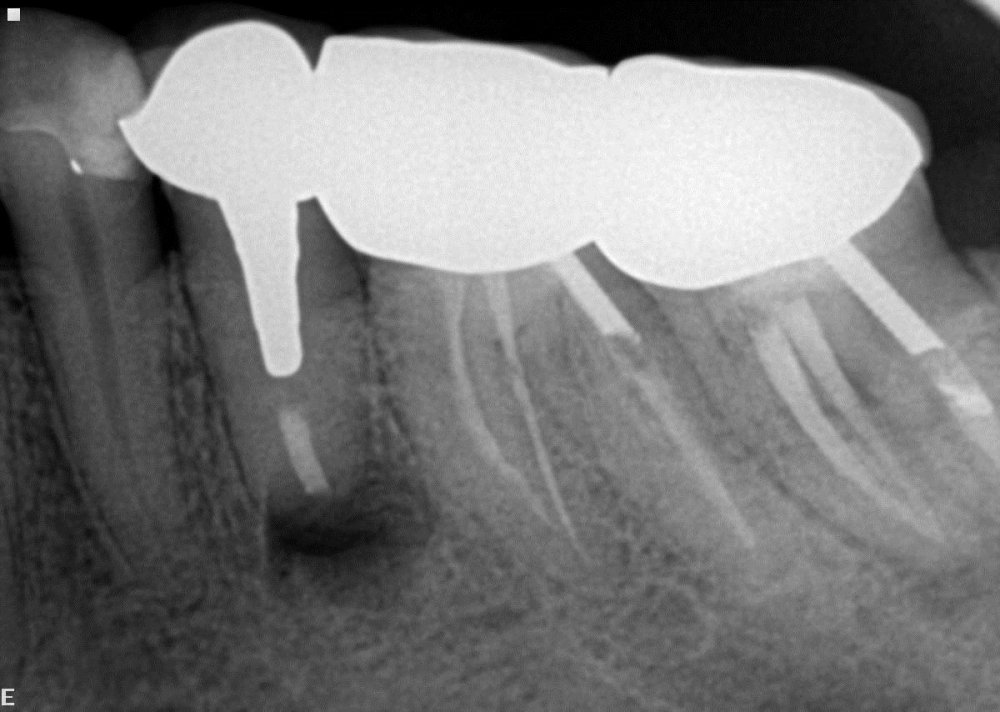

Endodontik müalicə (kanal müalicəsi) həyata keçirilən dişlərdə, kök kanallarının mürəkkəb konfiqurasiyası, yalnış və ya yetərsiz müalicə metodunun tətbiqi, bəzən də həkim səhvi/ehtiyatsızlığına bağlı olaraq təkrar iltihablanma – apikal ostit meydana çıxa bilir. Çox zaman bu tip iltihabi proseslər kliniki olaraq şikayətlərə səbəb olmadığından, zaman keçdikcə miqyasını genişləndirərək iltihab mənşəli odontogenik kistlərin yaranmasına gətirib çıxarır.

Bu zaman bəzi hallarda kanal müalicəsinin yenidən icrası (endodontik reviziya) mümkün olsa da, bir çox hallarda bu və ya digər səbəbdən həyata keçirilməsi mümkün olmur. Bu zaman əsas tətbiq edilən müalicə metodu dişi çəkməmək şərti ilə, iltihab ocağının uzaqlaşdırılmasını təmin edən – diş kökünün rezeksiyası metodudur. Bu əməliyyat vasitəsilə iltihab ocağı diş kökü ilə birlikdə kənarlaşdırılır və kök kanalları xüsusi metodla yenidən işlənir və doldurulur. Əməliyyat əsasən yerli ağrısızlaşdırma altında, xüsusi böyüdücü vasitənin tətbiqi ilə həyata keçirilir.